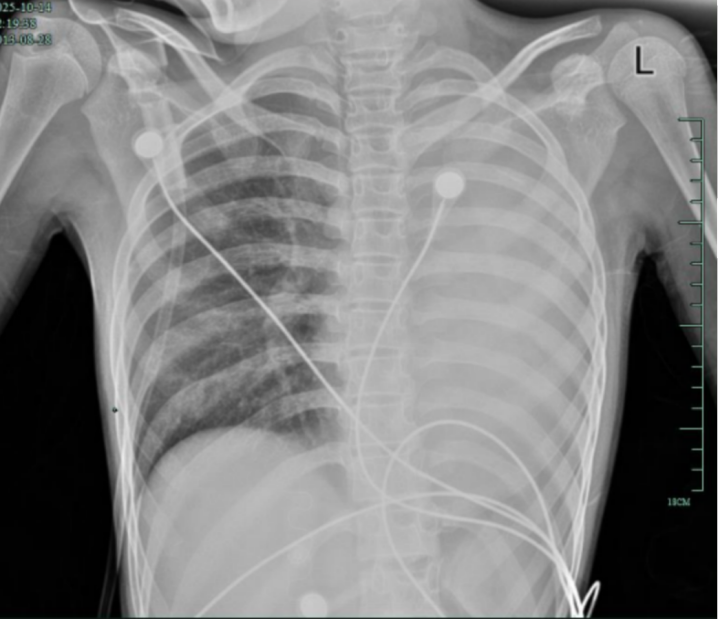

治疗前,左肺呈“白肺”状态

入院后,她很快出现呼吸急促、胸闷胸痛,只能靠5L/min的面罩吸氧维持血氧,胸片显示左肺已完全呈“白肺”改变,肺部炎症进展迅猛。